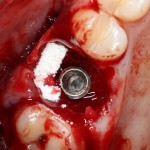

Все начинается с удаления зуба:

Обратите внимание на состояние вестибулярной стенки лунки. В проекции верхушек корней вы можете увидеть костный дефект, вызванный длительным воспалительным процессом (собственно, почему этот зуб пришлось удалять). В этом случае, вестибулярная стенка лунки неизбежно лизируется после удаления зуба, а это приведет не только к проблемам в эстетике, но и осложнит последующий уход за протетической конструкцией. Поэтому в данном случае мы должны продумать, в том числе, аугментацию лунки. И порядок действий здесь несколько иной, нежели в предыдущем случае.

Устанавливается имплантат Astratech (Dentsply Implants):

Для аугментации также используем Bio-Oss Collagen 100 mg, нарезаем его по размеру с помощью скальпеля и позиционируем в лунках щечных корней:

На имплантат ставим формирователь, ушиваем лунку. Напомню, что любой биоматериал должен быть герметично запечатан в ране (фактор успеха III). В противном случае, от него больше вреда, чем пользы: